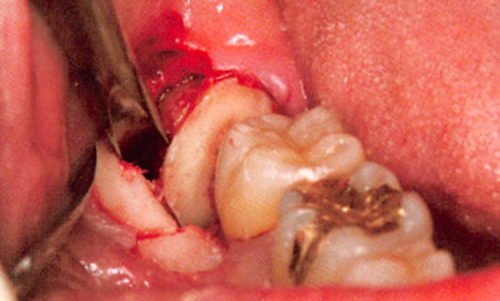

图1:下牙槽神经从下颌骨中穿出

在手术中进行翻瓣以暴露第三磨牙时,遇到了一些阻力。经过仔细检查,发现一根与骨膜瓣粘连的绳索状结构。将其轻轻分离后,确认该结构为下牙槽神经。该神经在距离口腔皮质骨外侧1.5厘米处穿出,且没有骨组织覆盖,随后重新进入下颌骨。

图4 分离后且非常清晰的下牙槽神经

下牙槽神经被提起后,骨板上的凹槽显露出来。进一步对CT图像进行检查,确认下颌神经从颊侧骨板穿出,并且在神经与囊肿之间存在正常骨质,下颌神经在一个开放的通道内自由移动。